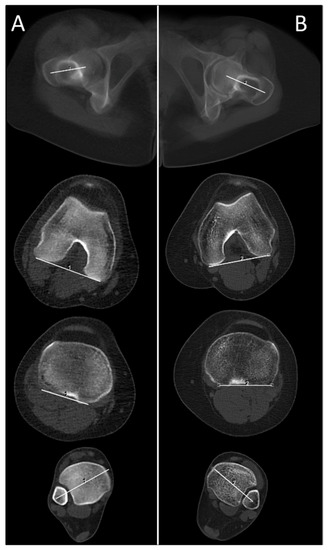

2.3. Technical Parameters of the HQ Protocol for CT Torsion Measurement of the Lower Limb

2.4. Technical Parameters of the New ULD Protocol for CT Torsion Measurement of the Lower Limb